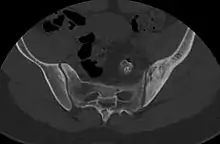

CT scan of primary B cell lymphoma in the left ilium, as diffuse cortical and trabecular thickening of the hemipelvis, mimicking Paget's disease.[2]